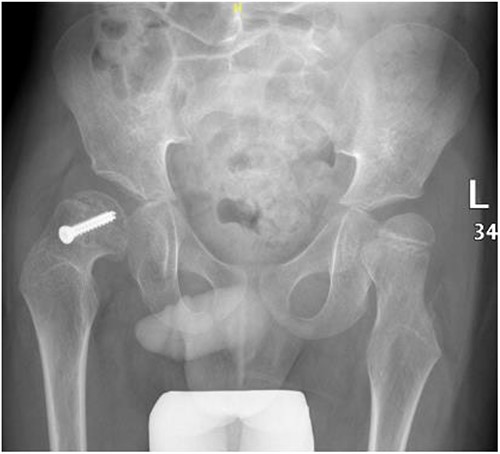

A 5-year-old independent ambulatory Middle Eastern boy with CP who was born preterm and developed grade III intraventricular haemorrhage and periventricular leucomalacia and was on AEDs, including valproic acid (VPA) and levetiracetam (LEV), for >3 years and was controlled over the last year (no history of seizure attack) presented to the emergency room (ER) with right hip pain and inability to bear weight for 4 weeks; the patient had no history of fever or trauma. Physical examination shows a thin, the weight is 12 kg, the height is 101 cm, vital signs within the normal range, tenderness over the right hip, and external rotation of the right hip, with restricted hip mobility. A radiological study was performed ~3 months before the patient presented to the ER for follow-up examination of a left hip coxa valgus deformity with no apparent abnormalities in the right hip (Fig. 1). Initial imaging studies conducted in the ER showed an anterior–posterior view of the pelvic radiograph, revealing Klein’s line [13] not intersecting the capital femoral epiphysis (Fig. 2), and frog-leg lateral view radiograph of the right hip (Fig. 3) confirmed SCFE and Southwick’s slip angle [13] of ~50° (moderate). Laboratory findings were clear for endocrine and renal diseases or infection, except for low vitamin D (total 25-OH Vitamin D: 43.4 nmol/L), suggesting vitamin D insufficiency. The diagnosis was confirmed with clinical and radiological studies as right-sided unstable SCFE requiring surgery. Surgical intervention was performed with percutaneous in situ fixation using a single fully threaded 4.5-mm cannulated screw (Fig. 4). Postsurgical rehabilitation included non-weight-bearing right lower extremities for 6 weeks. Regular follow-up with serial radiology studies showed stable fixation with no migration of screw or further slippage at 6 weeks (Fig. 5) and 3 (Fig. 6), 15 (Fig. 7), and 36 months (Fig. 8). During follow-up, a painless range of motion in the right hip was observed, with full weight-bearing and resumption of his usual activities with no complaints.

Right hip anterior–posterior radiograph, 36 months following post-operative fixation.